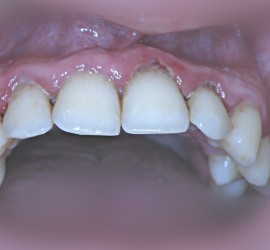

Аномалии строения и пороки развития зубов Пороки тканей зуба многообразны, они могут проявляться изолированно и сочетаться с аномалиями строения и пороками развития органов и систем всего детского организма, в том числе челюстно-лицевой области. Ткани зуба имеют эктодермальное (эмаль) и мезодермальное (дентин, пульпа, цемент) происхождение. В связи с этим пороки эмали […]